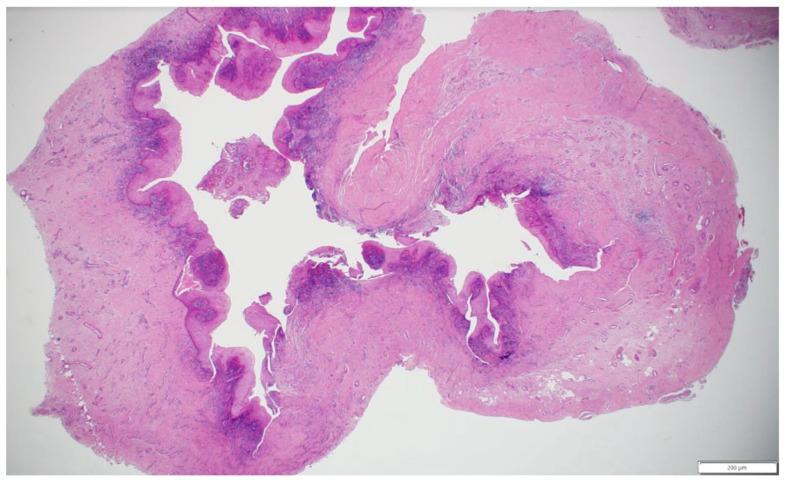

A 35-year-old male patient presented with a large periapical cystic lesion in the maxillary anterior region. Treatment involved marsupialization followed by cyst enucleation and GBR using a resorbable magnesium membrane and bovine xenograft. The magnesium membrane served as a structural support to bridge the bony discontinuity in the palatal bone. Cone-beam computed tomography (CBCT) was used for diagnosis, treatment planning, and follow-up assessments. At 16 months post-treatment, CBCT imaging revealed significant bone regeneration, with restoration of the palatal contour and cortication of the palatal wall. Clinical examination showed asymptomatic teeth with normal mobility and optimal soft tissue healing.

一名35岁男性患者上颌前部出现一个大的根尖囊性病变。治疗包括袋形术,随后进行囊肿摘除术,并使用可吸收镁膜和牛异种移植物进行引导骨再生。镁膜作为一种结构支撑物,用于桥接腭骨的骨不连续处。锥形束计算机断层扫描(CBCT)用于诊断、治疗计划制定和随访评估。治疗后16个月,CBCT成像显示骨再生显著,腭轮廓恢复,腭壁皮质化。临床检查显示牙齿无症状,松动度正常,软组织愈合良好。